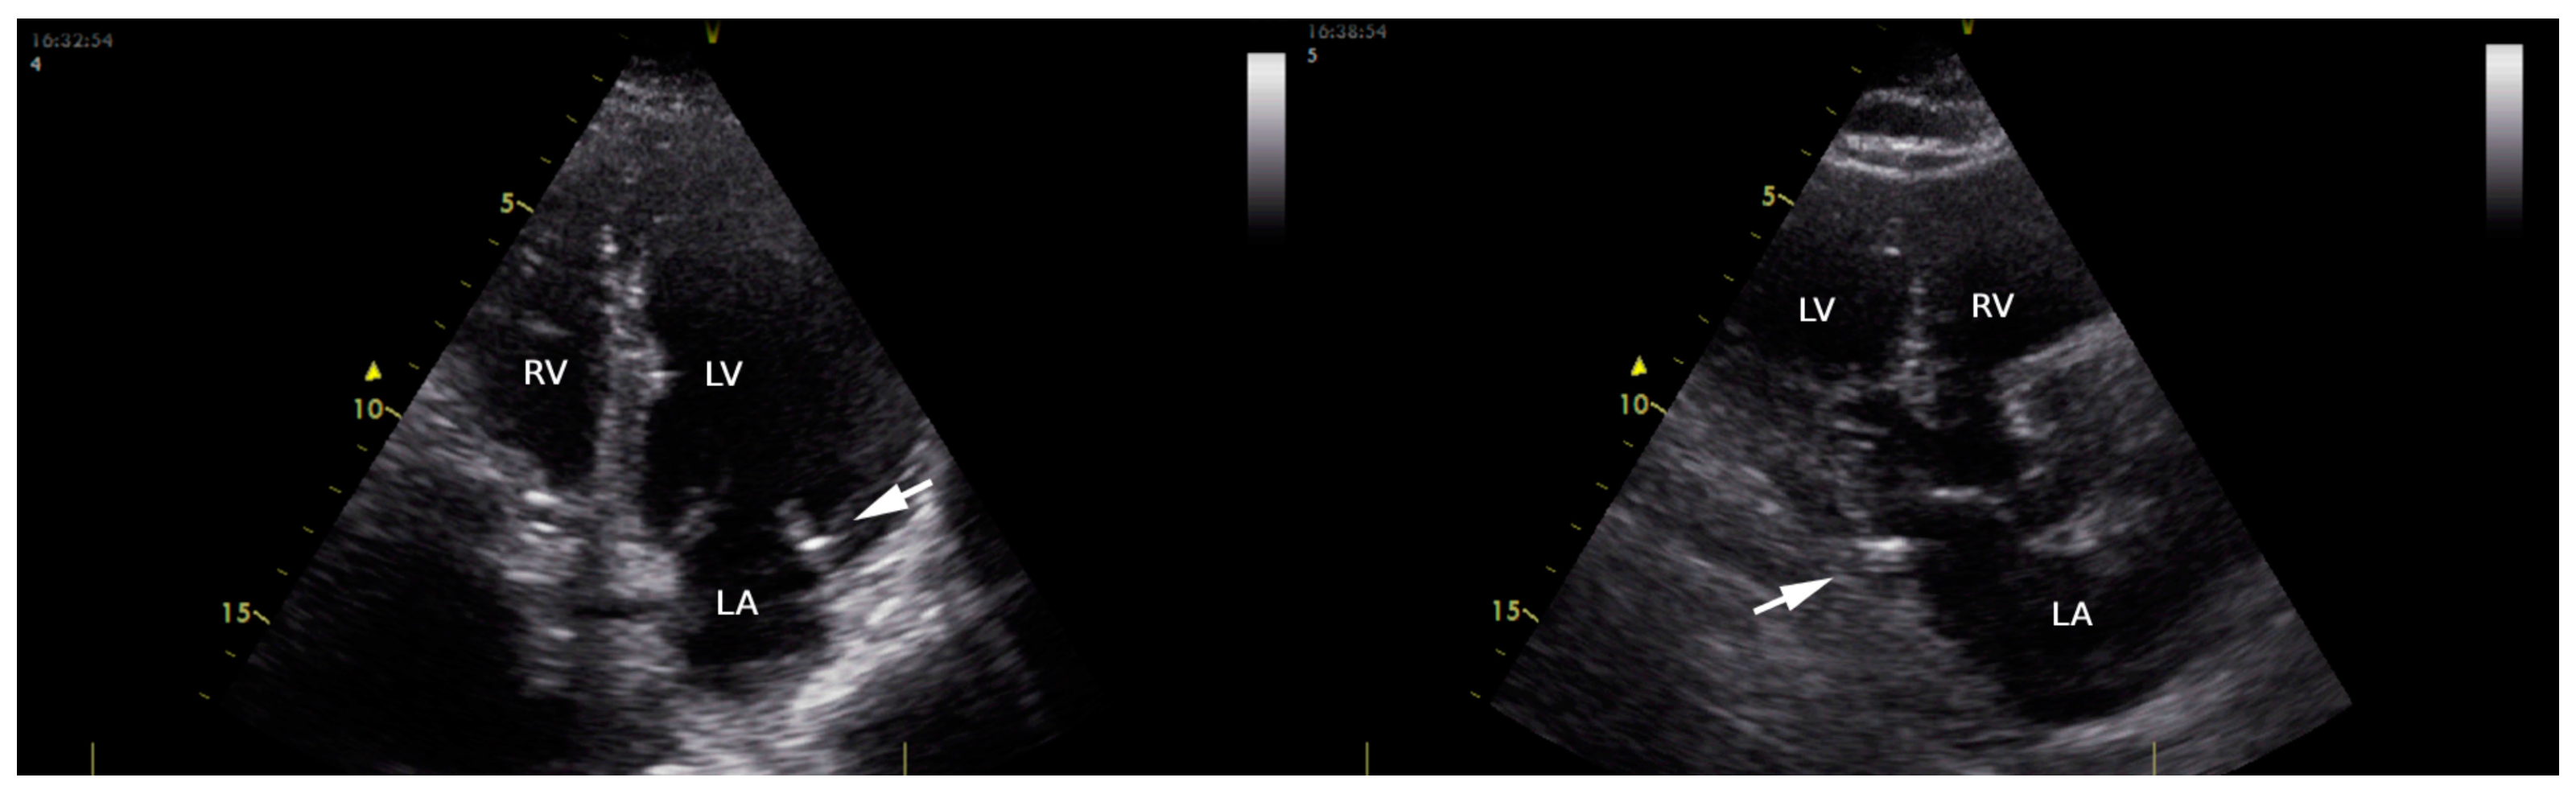

A cardiac structural and functional assessment, including the presence of MAC, was conducted via transthoracic echocardiography using a Vivid T8 Pro, GE Healthcare (according to the newest recommendations of the European Association of Cardiovascular Imaging) [10]. MAC (Figure 1) was defined as an echo-dense structure, located at the junction of the atrioventricular groove and the posterior or anterior mitral leaflet on the parasternal long-axis view; apical 4- or 2-chamber view; and parasternal short-axis view [11]. The parameters quantified during the transthoracic echocardiographic examination were as follows: left ventricular (LV) dimensions (interventricular septum—IVS, left ventricular posterior wall—LVPW, left ventricular end-diastolic diameter—LVEDD); LV systolic function (LV ejection fraction via Simpson method—LVEF), and LV diastolic function (E/A; E/e’; left atrium volume). E/A ratio was assessed in patients in sinus rhythm in apical 4- or 2-chamber view; E represents the maximum velocity of early diastolic filling of the mitral flow, and A represents the maximum velocity of the late diastolic filling of mitral flow. The diastolic index or E/e’ ratio (the ratio of early mitral in-flow to tissue velocity of the mitral annulus) was assessed in apical 4- or 2-chamber view in patients with AF (A wave being absent in these patients). We used the e’ velocity obtained via Tissue Doppler Imaging from the septal and lateral mitral annulus. For patients in AF during the echocardiographic examination, we used average velocity measurements taken during 10 consecutive cycles.

Figure 1.

Transthoracic echocardiography in apical four-chamber view (left) and long parasternal view (right), showing mitral annular calcification (arrow) in an enrolled patient. LA: left atrial; LV: left ventricle; RV: right ventricle.